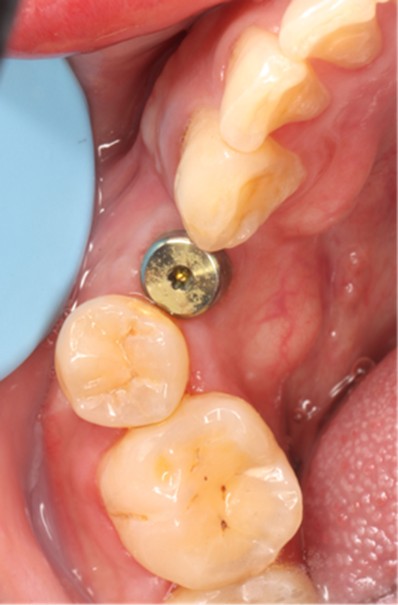

November 23, 2025: Implant follow-up examination. The implant surgical site showed excellent healing, with no abnormal bone density around the implant and satisfactory osteogenesis. The third-stage impression taking was implemented. The panoramic radiograph below confirmed the complete seating of the implant impression coping.